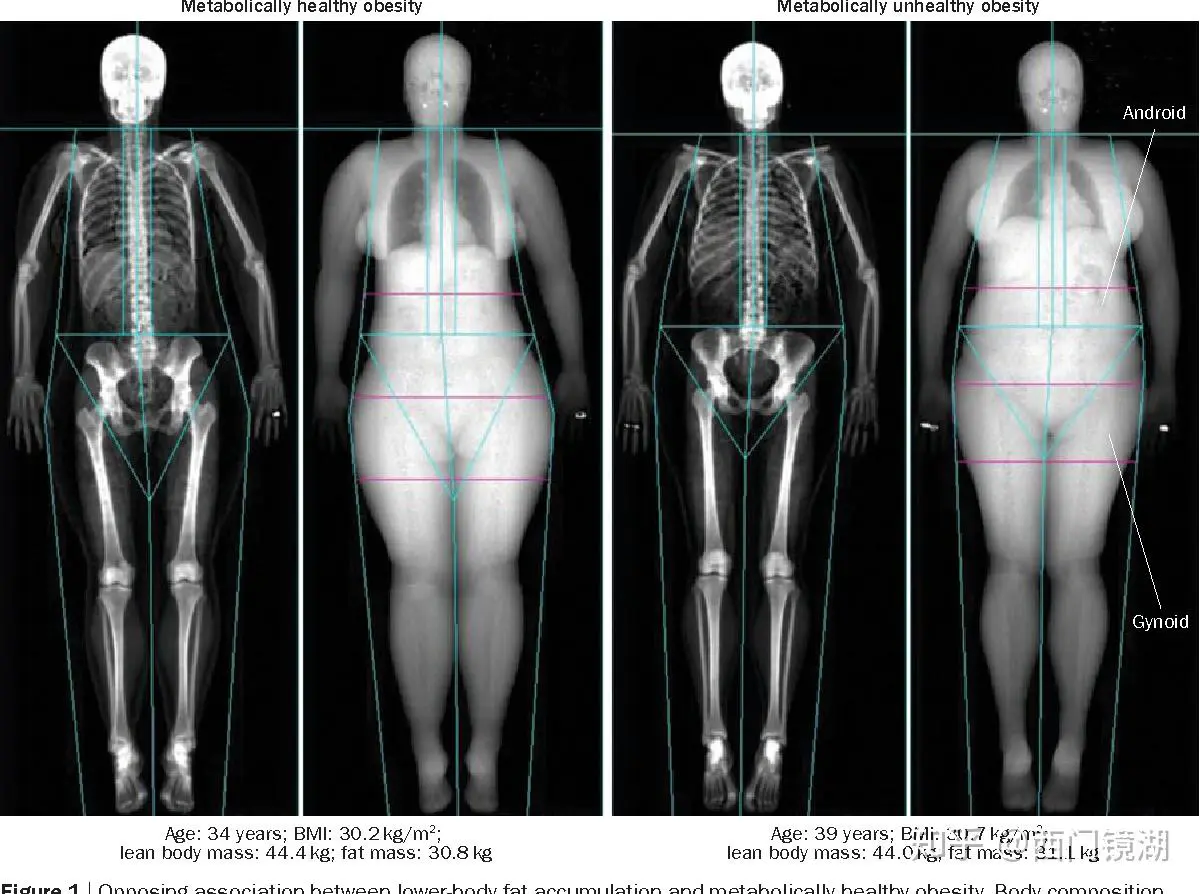

我们的肥胖又分成苹果型肥胖和梨形肥胖。

如果你胖的是屁股和大粗腿,恭喜你,你胖的是健康的,你不太可能是胰岛素抵抗。

看上图的两个姑娘,岁数差不多,体重差不多,体脂率差不多,但是左一是胖屁股的梨型身材,右一是胖腰的苹果型身材。

很可惜,你胖哪个位置是你天生决定的,不是后天可以更改的。

它是你新陈代谢的结果,而不是原因。